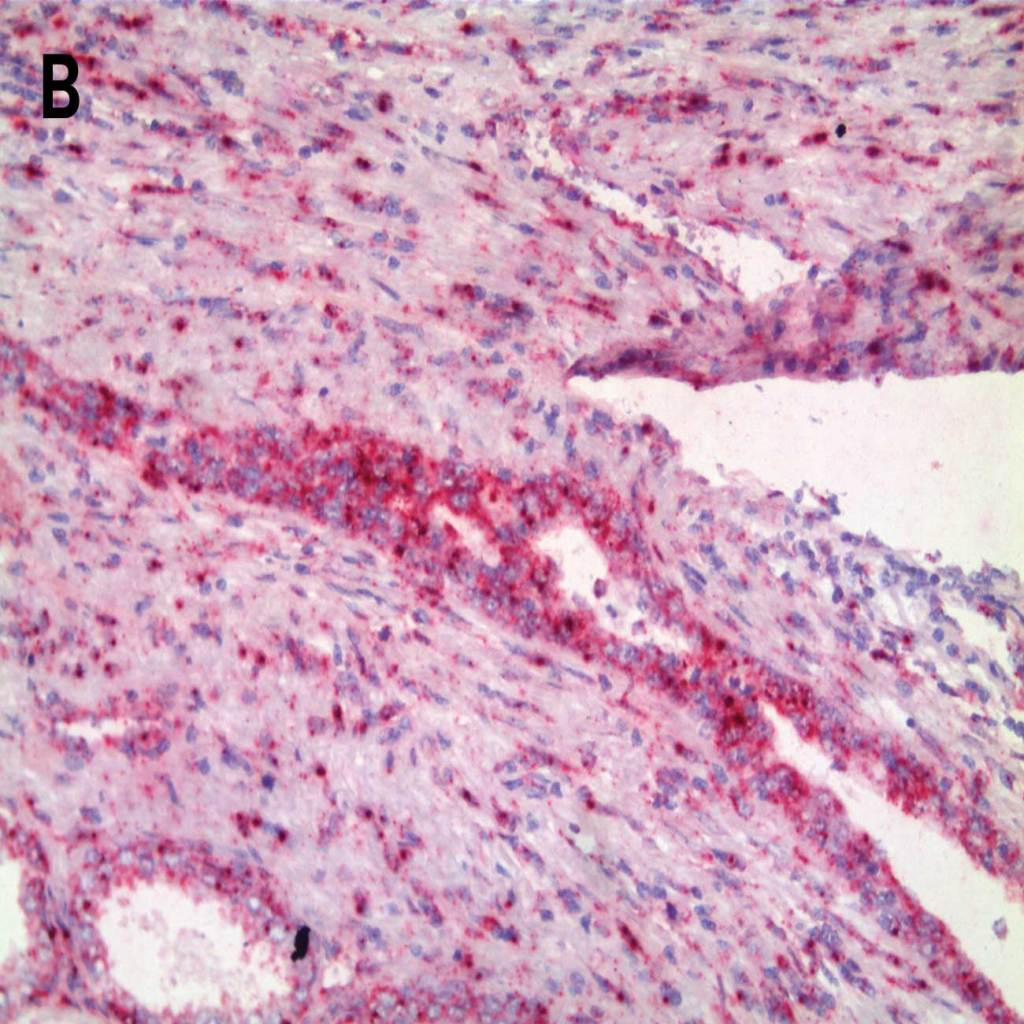

HER-2 detected in breast cancer tissue with A.-B. AMPIVIEW® HER-2 (AS) Dig RNA Probes and C.-D. with AMPIVIEW® NSP Dig RNA Probes (negative control probe). AMPIVIEW® RNA probes have been amplified with DIGX® rabbit anti-digoxigenin linker and detected with POLYVIEW® PLUS AP (anti-rabbit) reagent, combined with HIGHDEF® Red AP Chromogen Kit and counterstained with HIGHDEF® Hematoxylin.